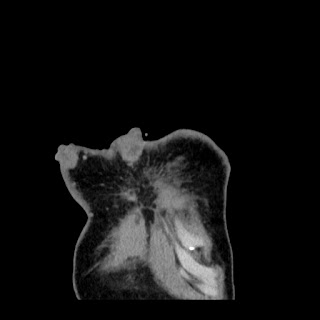

A 62 years old man with enlarged mole on chest since 2 months.

CT chest :-